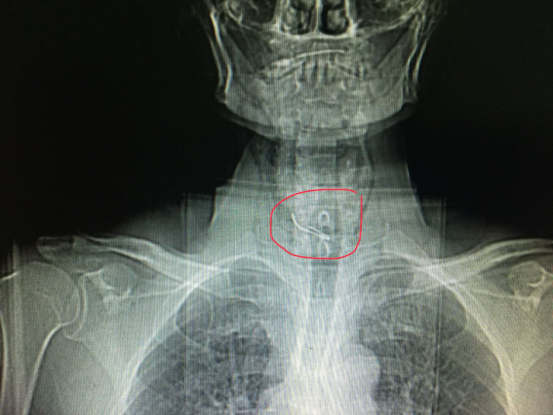

接诊的杨涛医生给予急查胸片、颈部CT提示:“胸1椎体见不规则金属物影,食管右侧壁见线状金属异物,穿出长度约0.8cm”。因假牙已经穿破食管壁,病人随时都有生命危险,情况危急,杨医生立邀麻醉科、耳鼻喉科、呼吸内科会诊。决定先行“内镜下食管异物取出术”。

杨医生使用当今最先进的奥林巴斯290超声内镜系统,成功取出长约2.5cm的假牙,拿给家属看时,他的儿子紧紧握着杨医生的手,连声说着“谢谢,谢谢”。经术后抗感染、胃肠减压、止血、抑酸、对症及支持等治疗,未出现其他并发症,患者于7月13日痊愈出院。